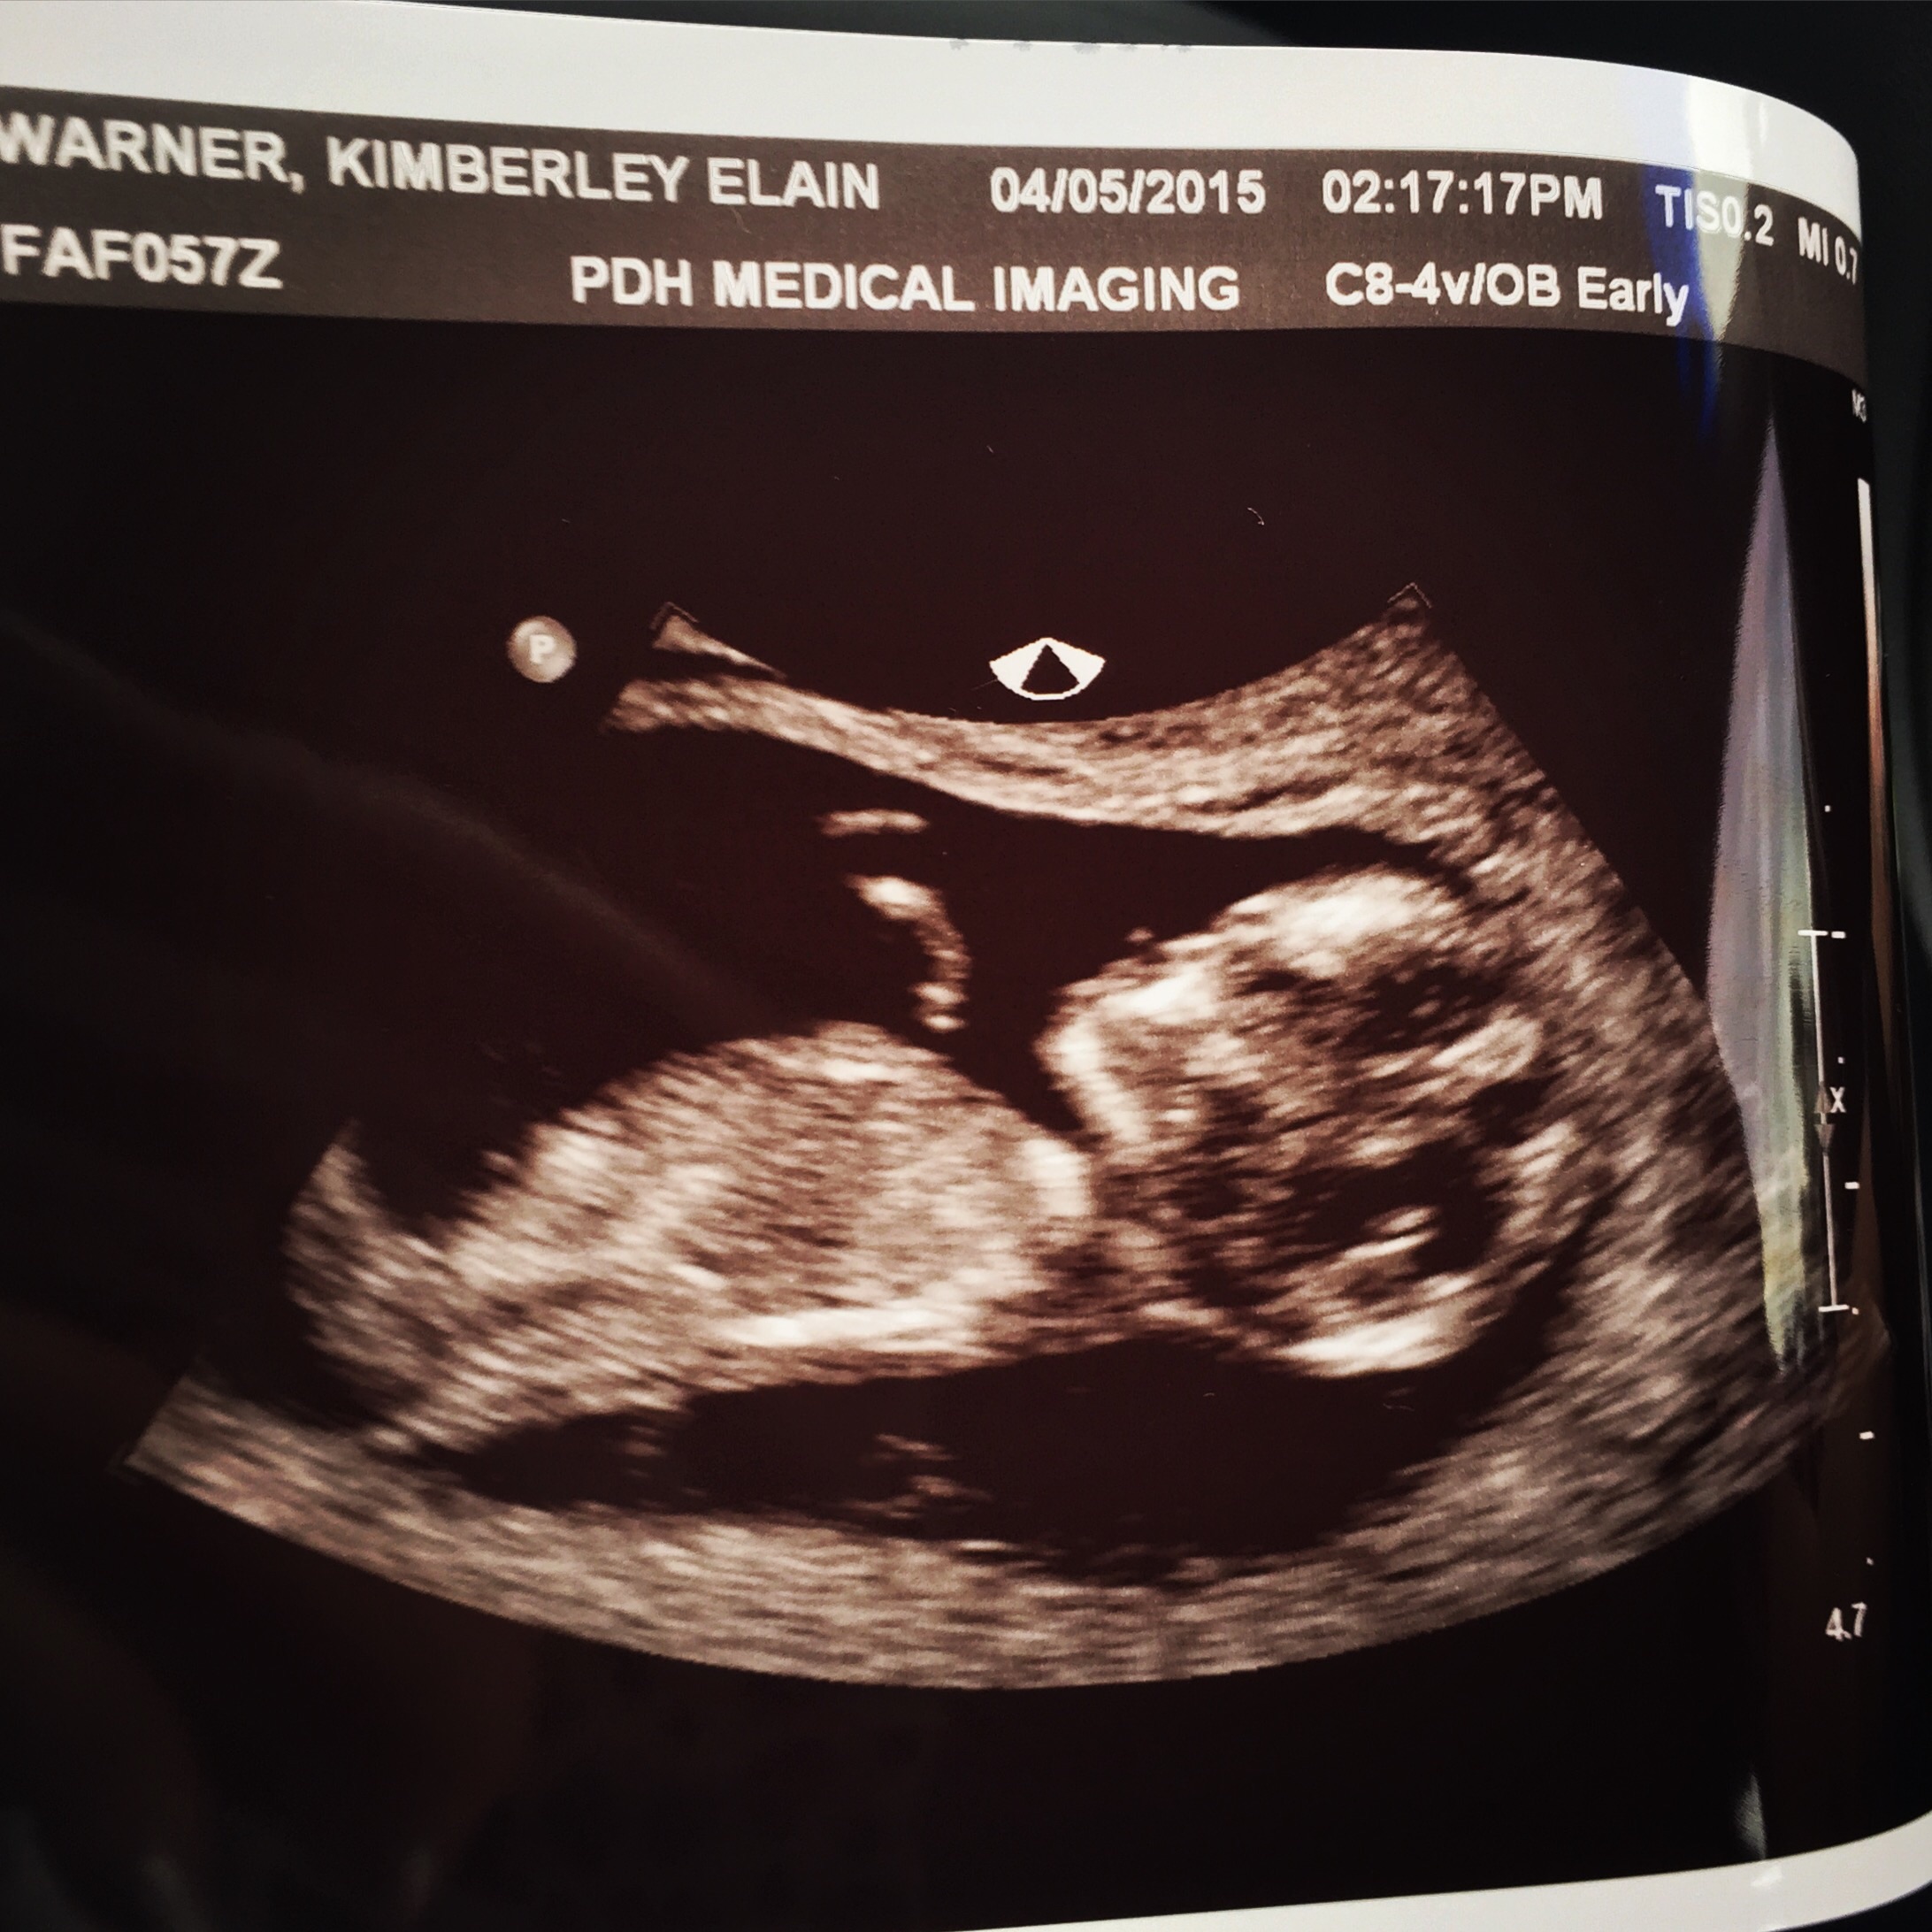

Had my ultrasound a week ago today!

Everything looked good from my end baby very active!

But I have just got off the phone to my dr who has ordered me for another scan due to thickness of the skull ect.

She is getting me to also do a blood test.